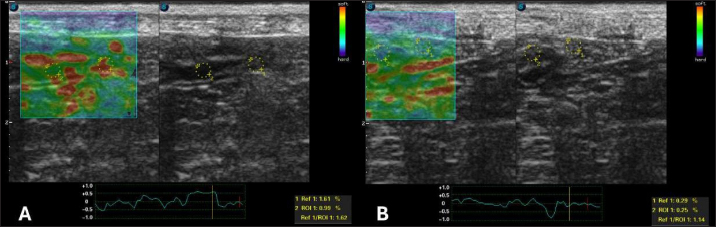

Fig. 3. Semiquantitative cross-sectional deformation elastography of the intestine of a dog with intestinal lymphangiectasia. The SR was obtained by evaluating ROI 1 of the mesenteric and ROI 2 of the dorsal region of the intestinal segment. A duodenum with an SR of 2.58 B-Jejunum with an SR of 1.97

After 30 days of treatment, there were no more laboratory changes (Table 2), the CCECAI was reduced to four (Table 1), and the patient no longer had diarrhea and gained weight. In addition, hyperechogenicity of the intestinal mucosa was reduced, and the values for elastography of the duodenum were as follows: ROI 1 1.61 % and ROI 0.99 %, with an SR of 1.62 (Fig. 5A). In the jejunum, ROI 1 measured 0.29 %, ROI 0.25%, and SR 1.14 (Fig. 5B).

Fig. 5. Semiquantitative elastography of deformation in a cross-section of the intestines of a dog with intestinal lymphangiectasia after 30 days of treatment. The deformation ratio (SR) was obtained by evaluating ROI 1 of the mesentery and ROI 2 of the dorsal portion of the intestinal segment. A duodenum with an SR of 1.62 B-Jejunum with SR=1.14.

Regarding elastographic aspects, no directly comparable veterinary studies have been conducted because there is no description of the strain elastography technique in dogs with this disease. A single analogous study provided reference data on the healthy jejunal mucosa of 60 dogs using shear wave elastography (Spużak et al., 2019). In this study, the mean values of the healthy animals were lower than those of the dogs with PLE. We therefore conclude that the stiffness of the intestinal mucosa is likely to increase, regardless of the elastography technique used. We suggest that this report serves as a basis for further research.

In human medicine, the results are similar to those observed in this report. Intestinal inflammation leads to an increase in the hardness rates seen on strain elastography, and after treatment, these parameters are reduced (Gabbiadini et al., 2021). Therefore, they are used for follow-up and as predictors of fibrosis. Despite the similarity, we did not reveal fibrosis in the duodenal mucosa.